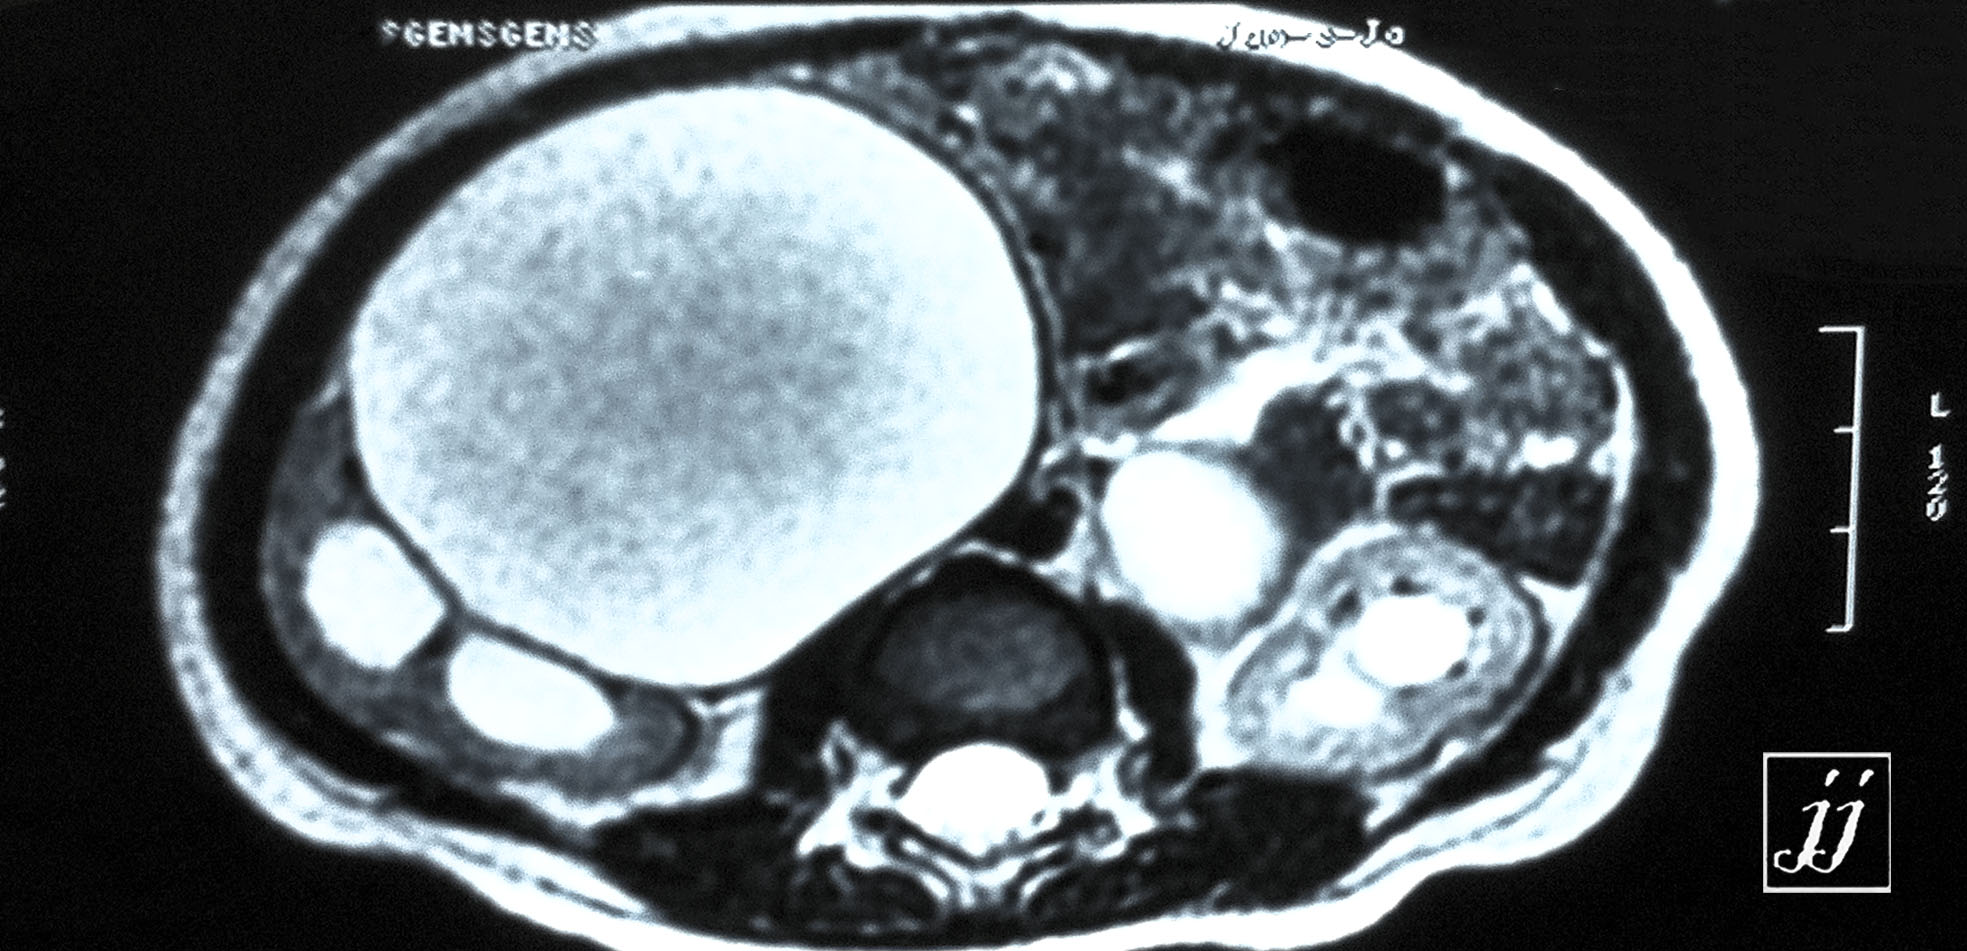

Abdomen- bi lateral hydronephrosis (3)